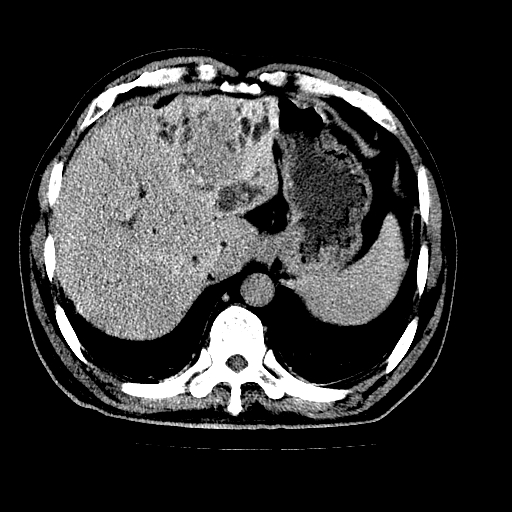

男,66岁,上腹部不适、黄染一周。彩超示:肝左叶占位,肝内胆管扩张,胆总管扩张,胆总管占位?

肝左叶不规则软组织肿块影,边缘不规整邻近肝实质受累分界不清;肝内胆管(左叶)明显扩张成“软藤状”,诊断:肝左叶胆管细胞癌。

肝左叶占位性病变,并胆管扩张,符合胆管细胞癌ct表现,门脉左支受累,左肾囊肿。窗宽太窄了,其他的看不清

左叶胆管细胞癌累及胆总管,门脉左支受侵,慢性胆囊炎胆结石,左肾小囊肿

肝左叶不规则软组织肿块影,边缘不规整邻近肝实质受累分界不清;肝内胆管(左叶)明显扩张成“软藤状”,诊断:肝左叶胆管细胞癌。胆囊钙乳症。